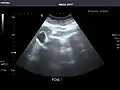

Left kidney -

Kidneys: Right and left kidneys measure 11.5 cm and 12 cm in length respectively. No hydronephrosis. Small left lower pole kidney cyst.